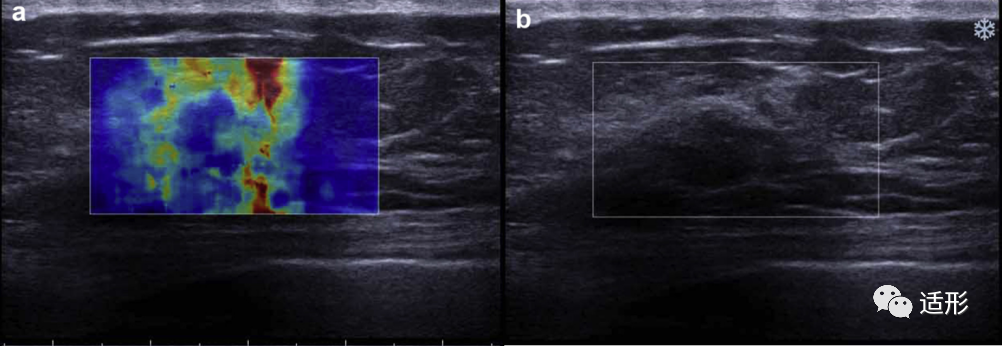

剪切波弹性成像(SWE)能定量的获取病变组织的弹性模量,通常选择平均弹性模量值(Emean)及最大弹性模量值(Emax)鉴别NML的良恶性。但目前不同学者对诊断NML良恶性截断值的选择有一定差异。Park等[2]选取Emean截断值为85.1 kPa。Wang等[3]选取Emax、Emean截断值为.81.07 kPa、63.71 kPa。Ko等[6]选取Emax、Emean截断值为69 kPa、41.6 kPa。这些差异可能是由于不同研究纳入NML样本组成或测量方式不同导致。SWE弹性图上“硬环征”的出现对诊断恶性NML有较高的特异性 (图3)。通过定量的测量病变周围组织(Shell)的弹性模量值也有助于判断NML的良恶性(图4)。Xu等[7]发现恶性NML病灶周围组织的弹性模量值高于良性病灶的周围组织,当病灶周围2.5mm的组织的Emax值以94.62 kPa为截断值时,诊断准确性可达87.44%。

图3. 59岁女性,常规超声提示非肿块型病变,剪切波弹性成像可见“硬环征”(病灶内部与周边组织相比,在病灶周边区域出现的局部硬度值增高区域,呈环状分布)。病理:浸润性导管癌[3]